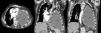

Ante la escasa mejoría clínica tras la evacuación de líquido pleural junto con los datos sugestivos de insuficiencia cardíaca derecha se realizó ecocardiografía transtorácica, objetivando una masa hipoecogénica en la pared inferolateral del ventrículo izquierdo, con dilatación de la aurícula izquierda, ligero derrame pericárdico, FEVI conservada y vena cava inferior dilatada sin colapso inspiratorio. Se realizó TC toracoabdominal, apreciándose una masa de partes blandas en la pared medial y caudal del hemitórax izquierdo, de 6×3cm, con infiltración pericárdica, efecto masa y pequeño derrame pericárdico asociado. Comparativamente con estudios previos se evidenció un importante incremento de la colección pleural conocida, que se encontraba ocupando la práctica totalidad del hemitórax, produciendo atelectasia compresiva del pulmón con desviación mediastínica contralateral y compresión cardíaca (fig. 1).

TC de tórax con contraste, corte axial (izquierda) y coronales (centro y derecha:): masa pleural en pared medial y caudal de hemitórax izquierdo con infiltración pericárdica (flechas continuas) y gran colección en hemitórax izquierdo correspondiente con piotórax crónico (flechas discontinuas), produciendo en su conjunto desplazamiento mediastínico contralateral y compresión cardíaca.